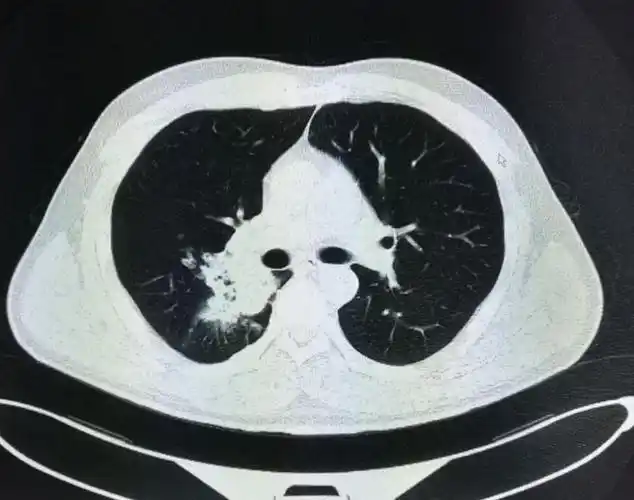

晚期肺癌的长期生存在坚持与关爱中实现

支气管肺癌怎么读片看看不同类型的支气管肺癌影像诊断